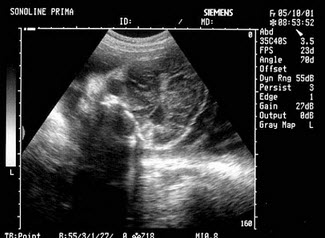

女性,29岁,停经28周,产前超声检查如图,最可能的诊断为()

A . 胎儿畸形,脑积水

B . 胎儿畸形,腹壁裂

C . 胎儿畸形,室间隔缺损

D . 胎儿畸形,无脑儿

E . 胎儿畸形,露脑畸形